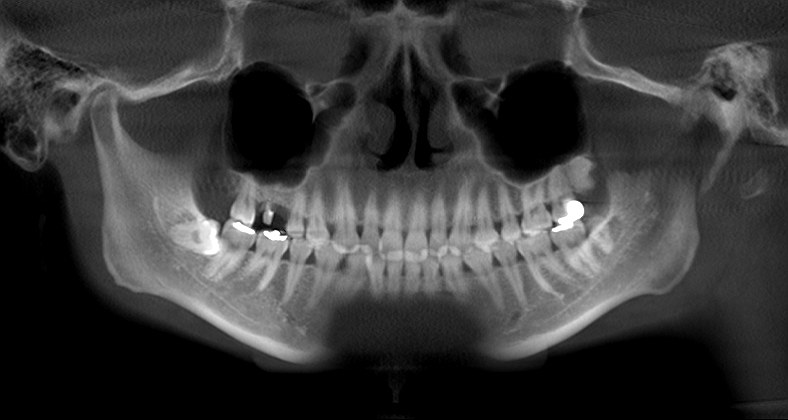

術前術後のパノラマになります

術前術後のパノラマになります